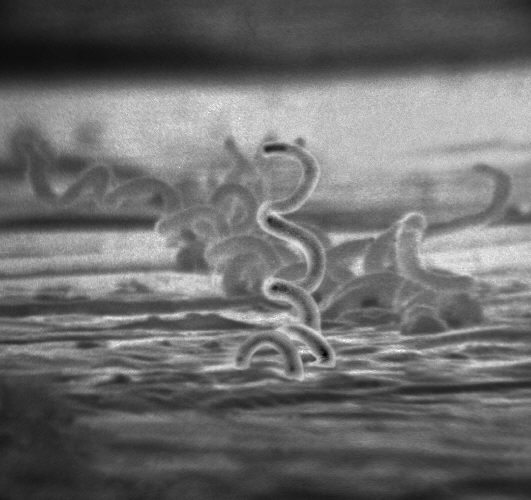

Il batterio Treponema pallidum responsabile della malattia (Centers for Disease Control and Prevention)